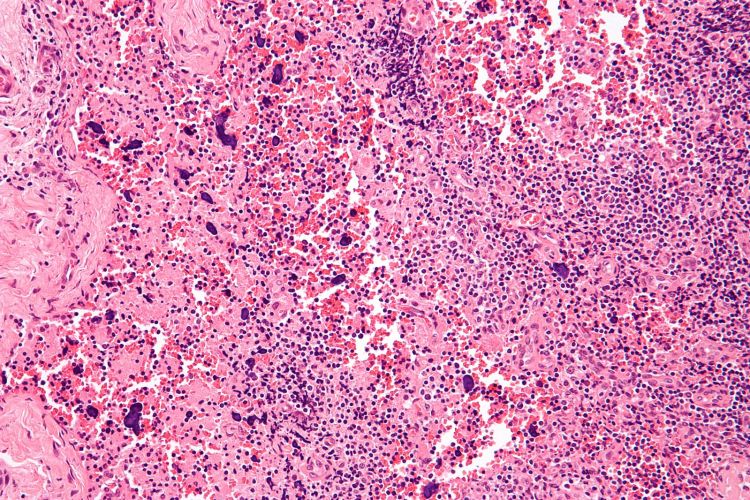

Photo caption: The image shows a high magnification micrograph of histomorphologic changes in a lymph node due to systemic lupus erythematosus. Public domain photo CC BY-SA 3.0 courtesy of Michael Bonert.